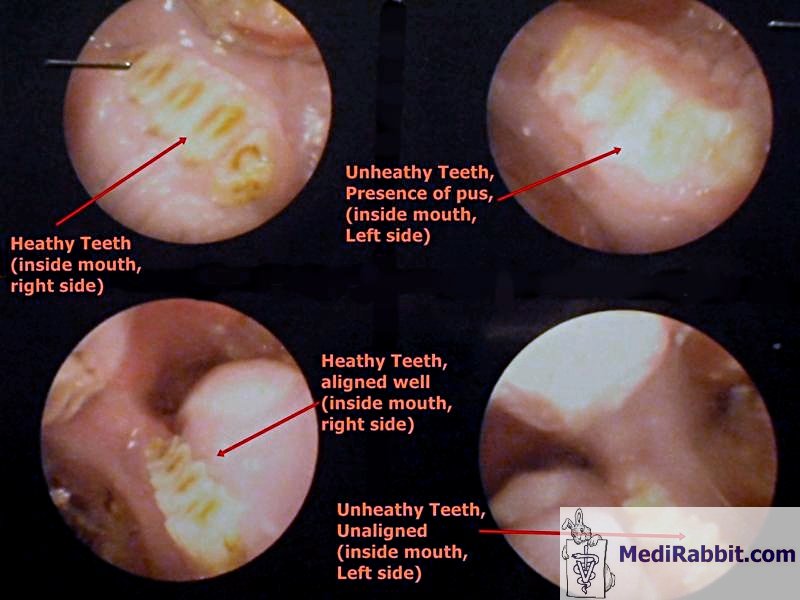

Jeżeli badanie wzrokowe i dotykowe wskazują na

obecność szczękowego lub żuchwowego ropnia, jama ustna

królika musi być dokładnie zbadana. Najlepiej wykonać to badanie

na króliku po podaniu mu środków uspakajających lub na

uśpionym króliku.